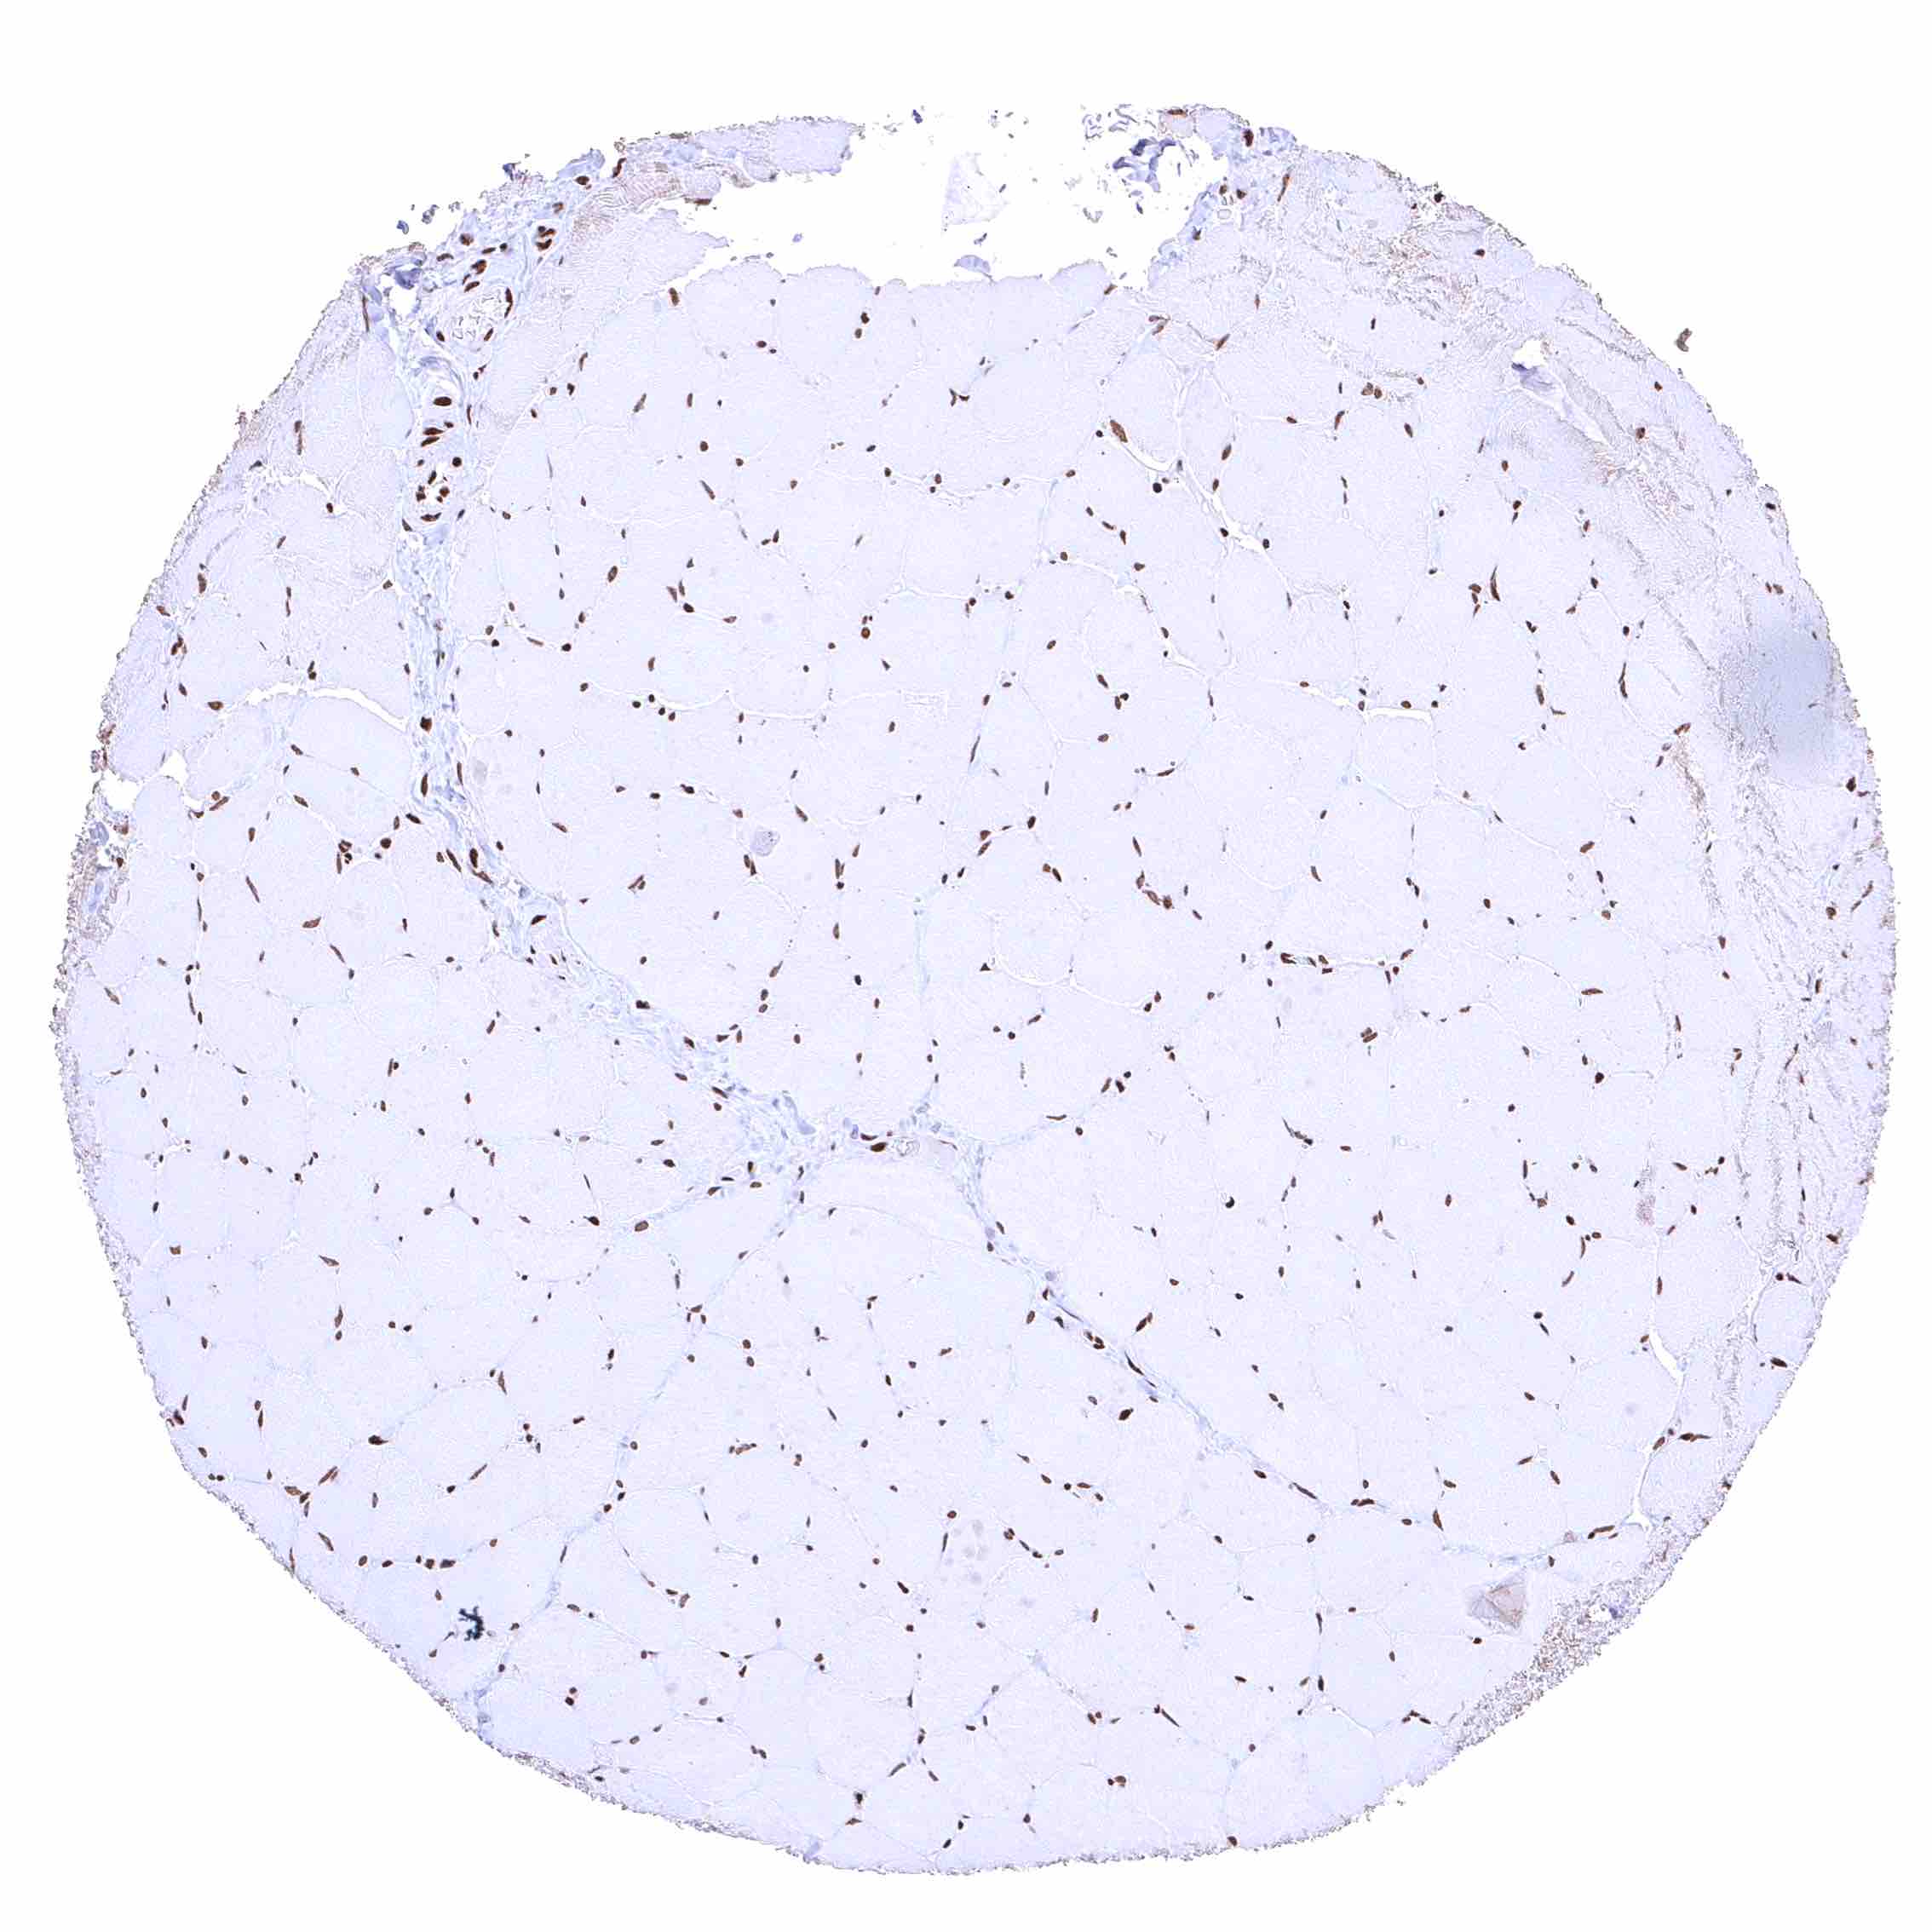

Fat – Distinct nuclear BRD4 staining of fat cells.